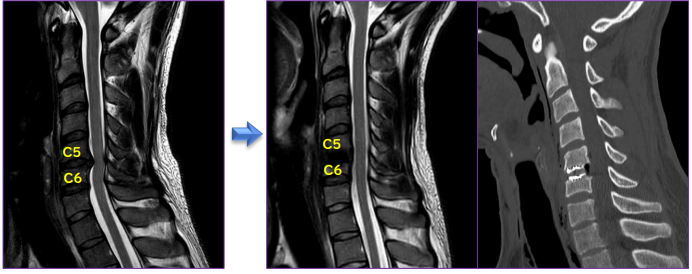

A.前からの手術(頚椎前方除圧固定術)

首の前面の皮膚を横切開し(1椎間であれば2.5~3cm程)で、椎体の前面を露出します。椎間板を取り除き、椎体後方骨棘、後縦靭帯を取り除いて脊柱管を広げ、上下の椎体を固定します。